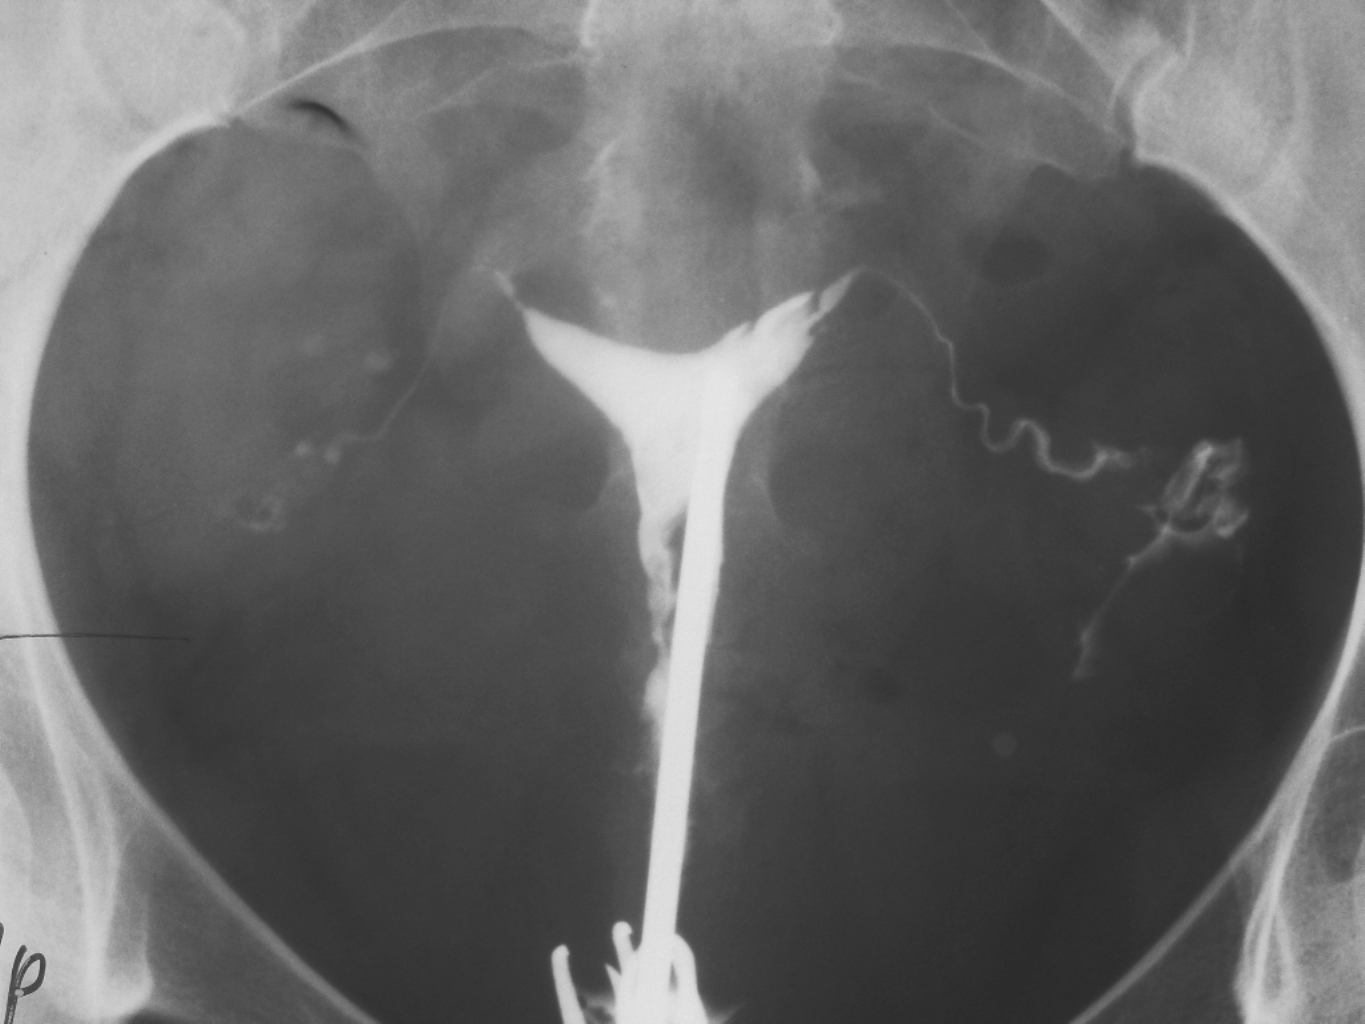

Гистеросальпингография: описание и фотографии